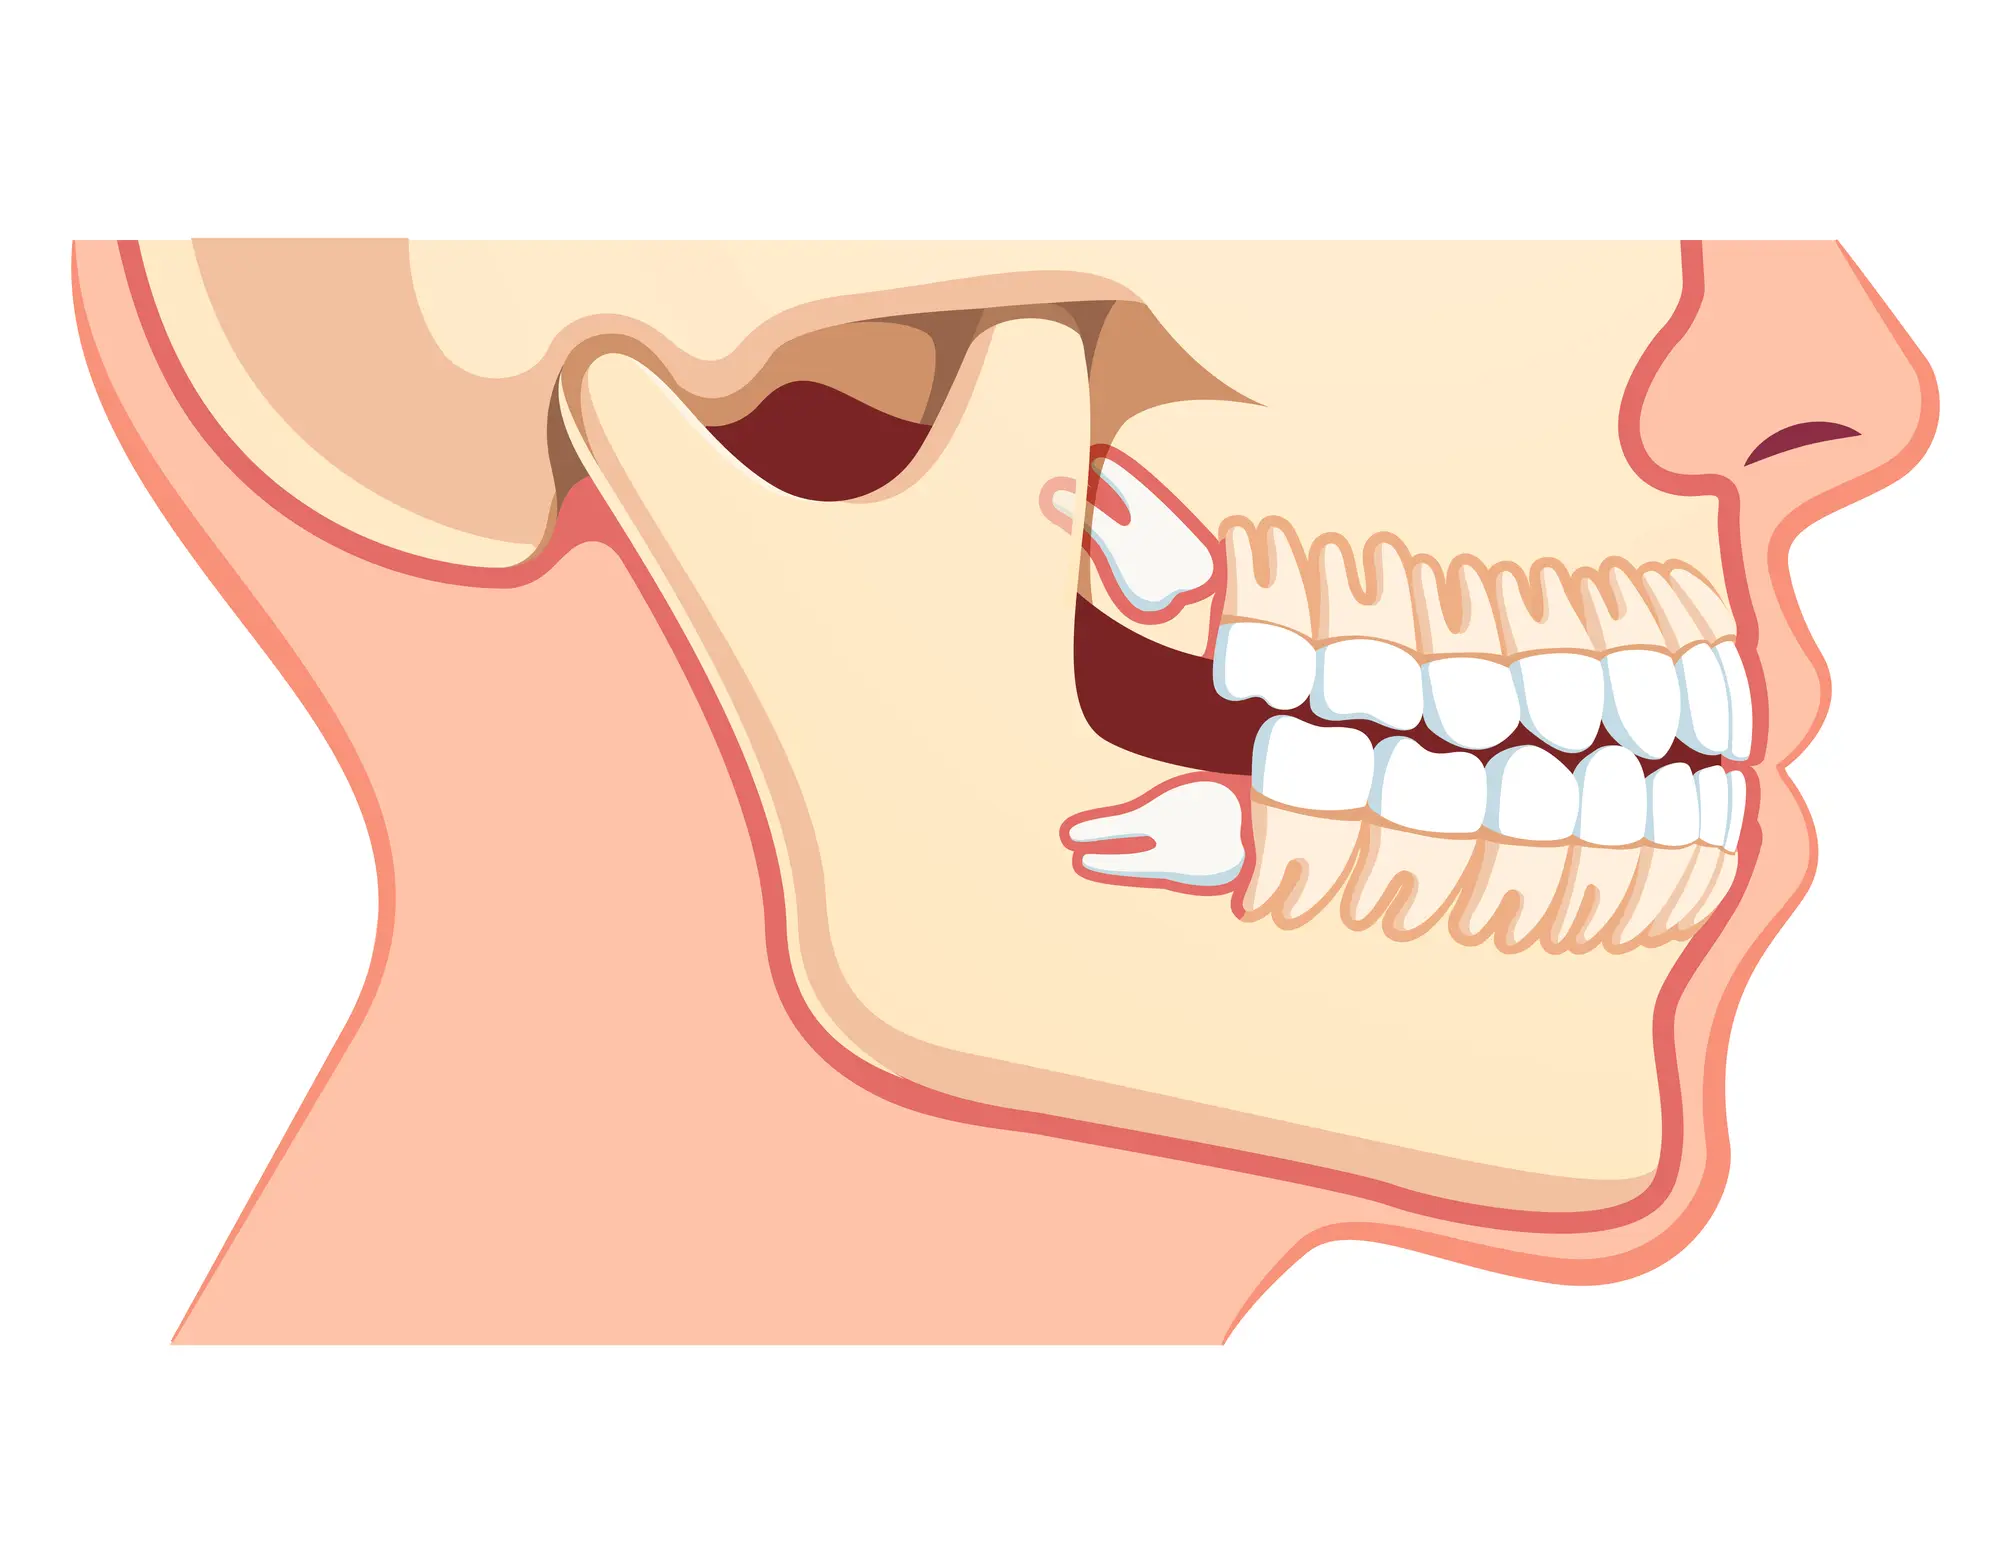

Wisdom teeth are the third set of molars, usually appearing between the ages of 17 and 25. Some people have all four, some have fewer, and others may not develop them at all.

They often emerge long after the rest of your adult teeth have come in, causing problems if there isn’t enough space in the jaw.

However, many people experience crowding, impaction (when the tooth doesn’t fully emerge), or increased risk of infection and decay. Regular exams and X-rays help determine whether your wisdom teeth could cause future problems.

On the day of your procedure, our team will review your anesthesia options and confirm that you're comfortable before we begin. Depending on the position of your wisdom teeth, removal may involve a simple extraction or a surgical approach if the teeth are impacted.